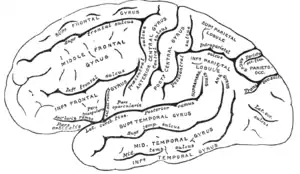

The cerebrum, consisting of the cerebral hemispheres, forms the largest part of the brain and overlies the other brain structures.[7] The outer region of the hemispheres, the cerebral cortex, is grey matter, consisting of cortical layers of neurons. Each hemisphere is divided into four main lobes – the frontal lobe, parietal lobe, temporal lobe, and occipital lobe.[8] Three other lobes are included by some sources which are a central lobe, a limbic lobe, and an insular lobe.[9] The central lobe comprises the precentral gyrus and the postcentral gyrus and is included since it forms a distinct functional role.[9][10]

Cerebrum

The cerebrum is the largest part of the brain and is divided into nearly symmetrical left and right hemispheres by a deep groove, the longitudinal fissure.[16] Asymmetry between the lobes is noted as a petalia.[17] The hemispheres are connected by five commissures that span the longitudinal fissure, the largest of these is the corpus callosum.[7] Each hemisphere is conventionally divided into four main lobes; the frontal lobe, parietal lobe, temporal lobe, and occipital lobe, named according to the skull bones that overlie them.[8] Each lobe is associated with one or two specialised functions though there is some functional overlap between them.[18] The surface of the brain is folded into ridges (gyri) and grooves (sulci), many of which are named, usually according to their position, such as the frontal gyrus of the frontal lobe or the central sulcus separating the central regions of the hemispheres. There are many small variations in the secondary and tertiary folds.[19]

The cortex is mapped by divisions into about fifty different functional areas known as Brodmann's areas. These areas are distinctly different when seen under a microscope.[21] The cortex is divided into two main functional areas – a motor cortex and a sensory cortex.[22] The primary motor cortex, which sends axons down to motor neurons in the brainstem and spinal cord, occupies the rear portion of the frontal lobe, directly in front of the somatosensory area. The primary sensory areas receive signals from the sensory nerves and tracts by way of relay nuclei in the thalamus. Primary sensory areas include the visual cortex of the occipital lobe, the auditory cortex in parts of the temporal lobe and insular cortex, and the somatosensory cortex in the parietal lobe. The remaining parts of the cortex are called the association areas. These areas receive input from the sensory areas and lower parts of the brain and are involved in the complex cognitive processes of perception, thought, and decision-making.[23] The main functions of the frontal lobe are to control attention, abstract thinking, behaviour, problem-solving tasks, and physical reactions and personality.[24][25] The occipital lobe is the smallest lobe; its main functions are visual reception, visual-spatial processing, movement, and colour recognition.[24][25] There is a smaller occipital lobule in the lobe known as the cuneus. The temporal lobe controls auditory and visual memories, language, and some hearing and speech.[24]